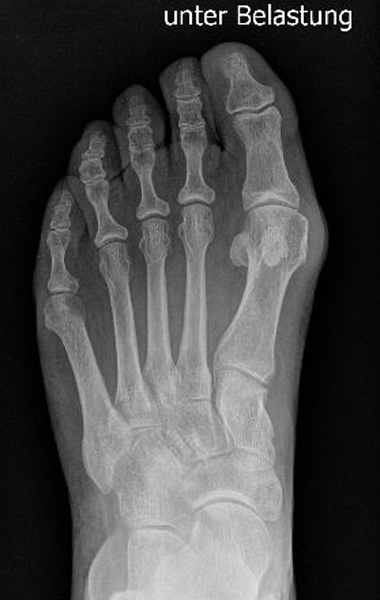

• Konventionelle Röntgenbilder mit Belastung im Stehen a.p. und seitlich, ggf. schräg.

• Beurteilung der Metatarsale V Form und Auswahl des geeigneten Operationsverfahrens.

Abb. 12a: Typ III Deformität präoperativ im belasteten dp Röntgenbild.